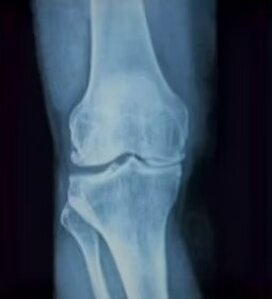

L’impianto di una protesi di ginocchio o artroplastica del ginocchio consiste nel rivestire le superfici

ossee senza più cartilagine di femore e tibia con un metallo poroso che favorisce l’integrazione con

l’osso. Tra le due nuove superfici viene interposto un inserto di plastica dura e inerte (polietilene ) a

ricreare una articolazione liscia e scorrevole.